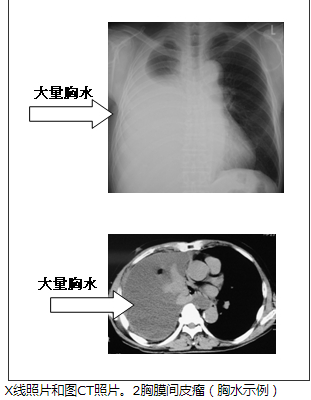

许多胸膜间皮瘤的被认为是由于石棉(石棉)抽吸。石棉,建材(建筑物),摩擦材料(刹车),管(水和污水管道),因为这被广泛使用,例如绝热材料(锅炉),职业,谁都能参与其定期检查必须注意,如接收(建立关系,管道,锅炉工作,造船等)。胸片和CT照片中,在被认为是胸腔积液(图2)和胸膜增厚(图3)的情况下,它可能是一个更详细的检查可疑胸膜间皮瘤。